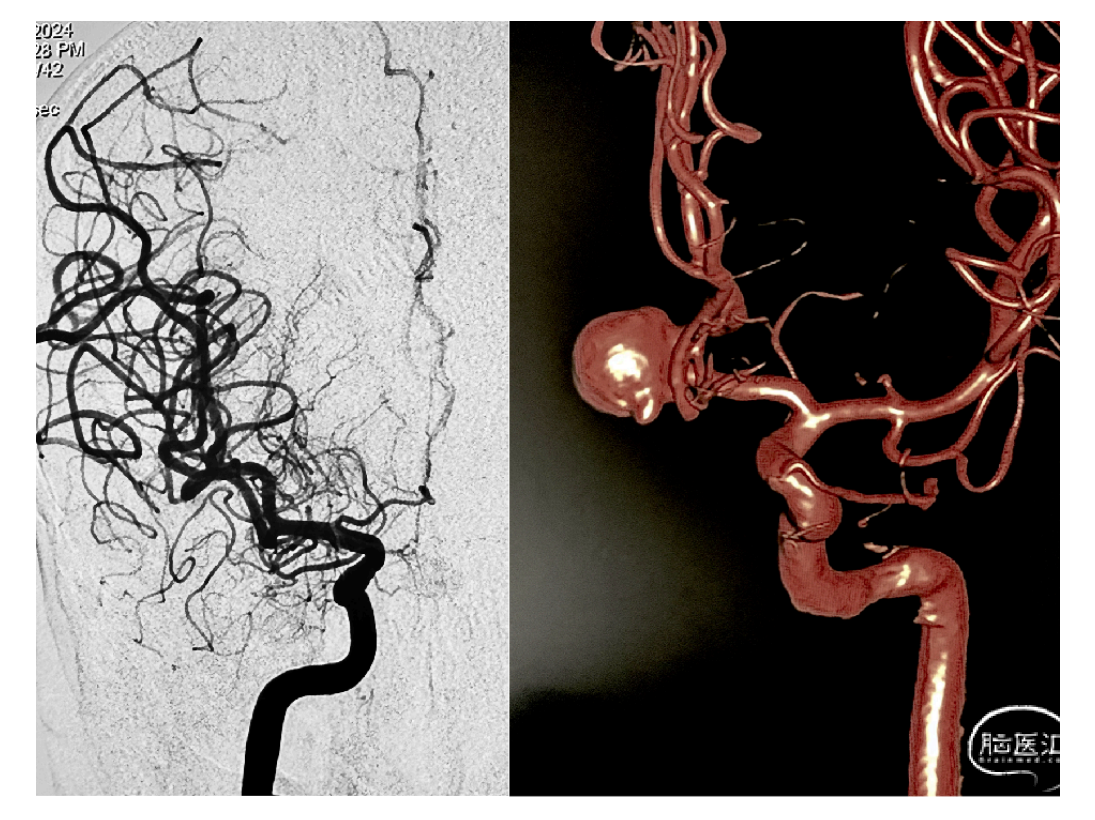

本期脑医汇为大家分享:天津市环湖医院【佟小光教授】的精彩病例内容:纵裂入路-前交通大动脉瘤夹闭术,欢迎阅读和分享!病例视频观看点击图片观看视频讲者:佟小光讲题:纵裂入路-前交通大动脉瘤夹闭术病例内容截图声明:脑医汇旗下神外资讯、神介资讯、神内资讯、脑医咨询、Ai Brain 所发表内容之知识产权为脑医汇及主办方、原作者等相关权利人所有。投稿邮箱:NAOYIHUI@163.com 未经许可,禁止进行转载、摘编、复制、裁切、录制等。经许可授权使用,亦须注明来源。欢迎转发、分享。